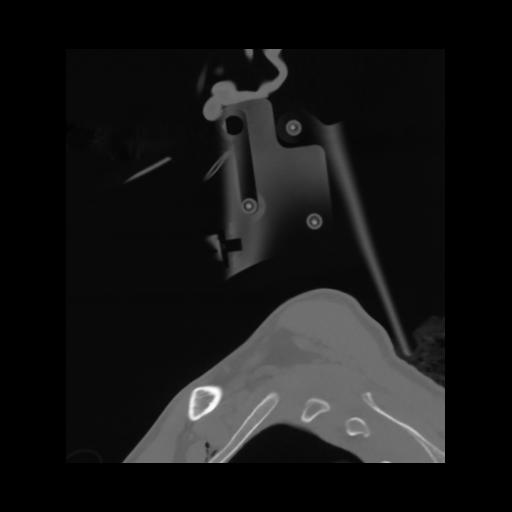

14 P.BLANDAS,,Sagittal,2.000,P.BLANDAS,Sagittal,